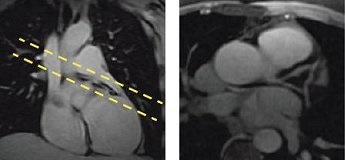

Figure 1. Coronal localizer with prescription (left), LCA (right)